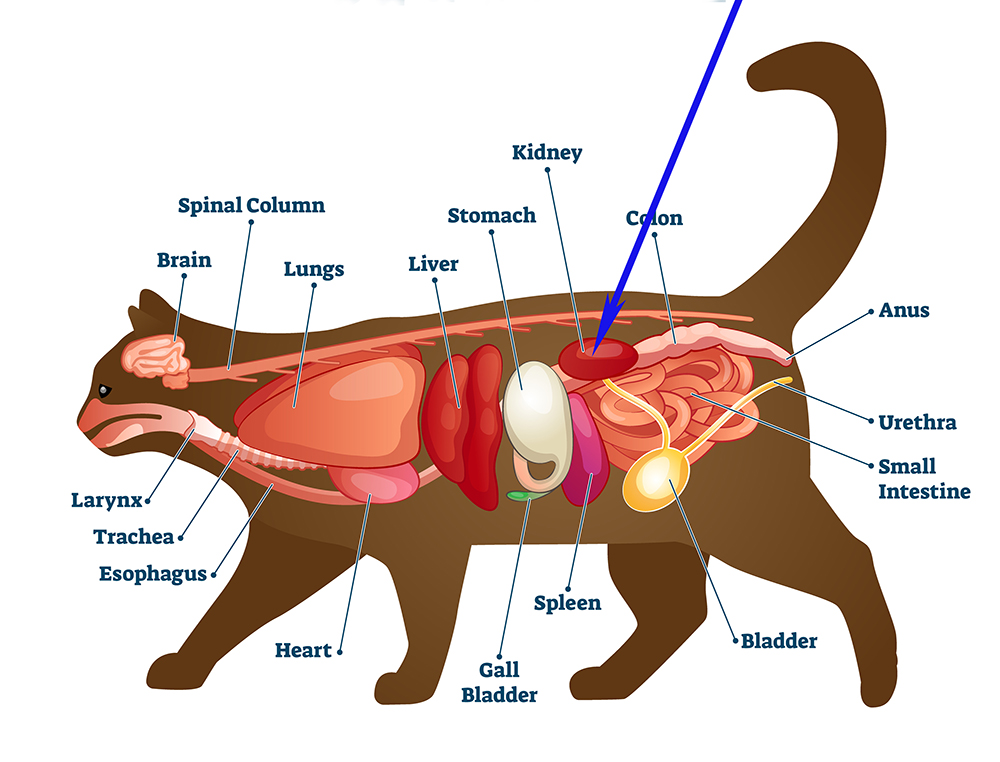

Mijn kat heeft een nierprobleem, wat te doen?

Wanneer uw kat gediagnostiseerd wordt met een nierprobleem, betreft dit vaak chronisch nierfalen. Bij katten komt dit helaas vaak voor: 1-3% van de katten krijgt hiermee te maken. Dit percentage stijgt tot wel 80% bij de oudere kat.

Bij chronisch nierfalen verliezen de nieren met verloop van tijd hun functie. De oorzaak is helaas vaak lastig te achterhalen maar er kan bijv. sprake zijn van een aangeboren afwijking, infectie of uitdroging. Door middel van een echo van de urinewegen kan meer informatie worden verkregen over een mogelijke oorzaak.

Een belangrijke taak van de nieren is het filteren van afvalstoffen uit het bloed en deze afvalstoffen afvoeren met de urine. Wanneer er sprake is van nierfalen worden de afvalstoffen niet meer goed uit het bloed gefilterd en zullen deze zich opstapelen. Hierdoor zal de kat zich ziek voelen en dit laten zien door bijvoorbeeld sloomheid, slechte vachtverzorging, verminderde eetlust en gewichtsverlies.